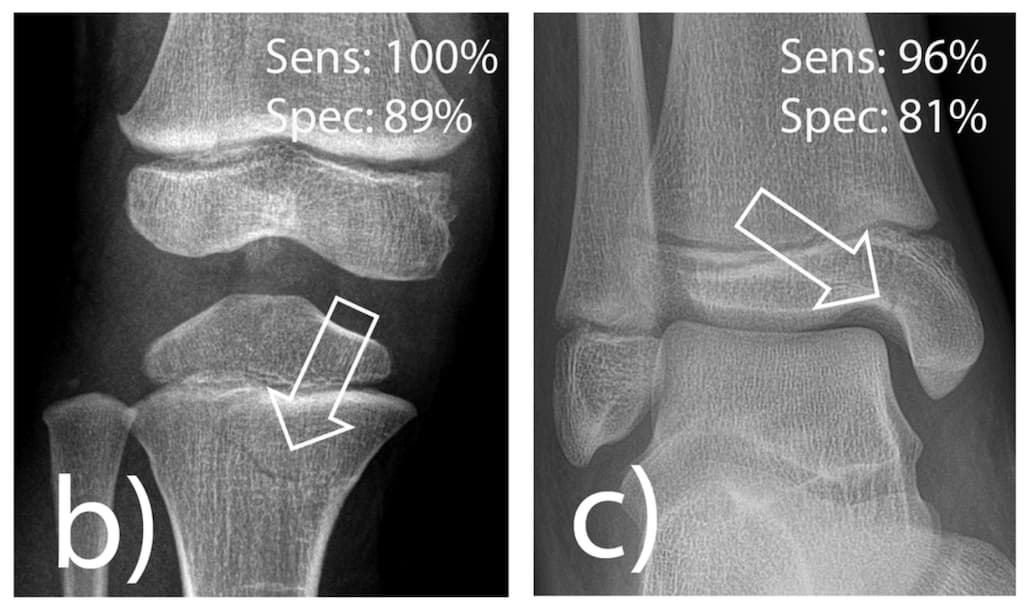

En traumatologie pédiatrique, les solutions d’IA ne pas toujours pertinentes pour assister les praticiens qui cherchent à identifier une anomalie musculo-squelettique. Des chercheurs allemands ont publié un article dans la Revue European Radiology dans lequel ils évaluent les performances d’un algorithme dédié ainsi que son apport pour les médecins juniors en pratique clinique.